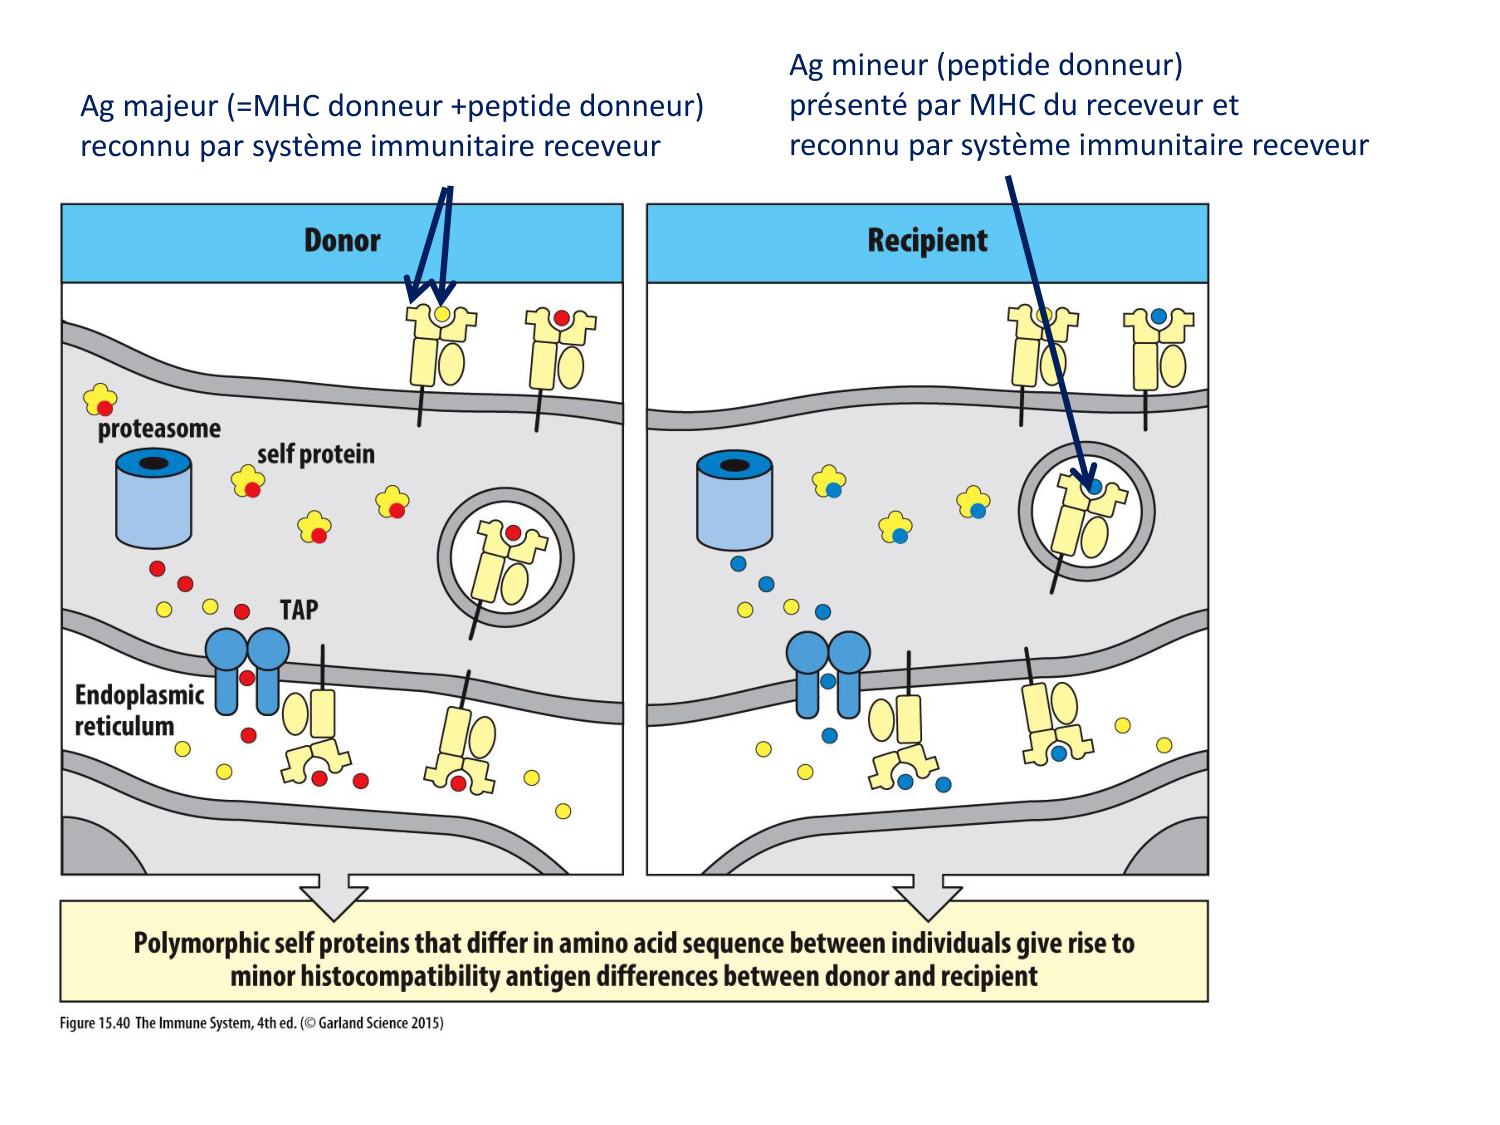

SMB4 Systèmes physiologiques 2 Immunologie, inflammation, transplantation · 61 pages · 8 sections